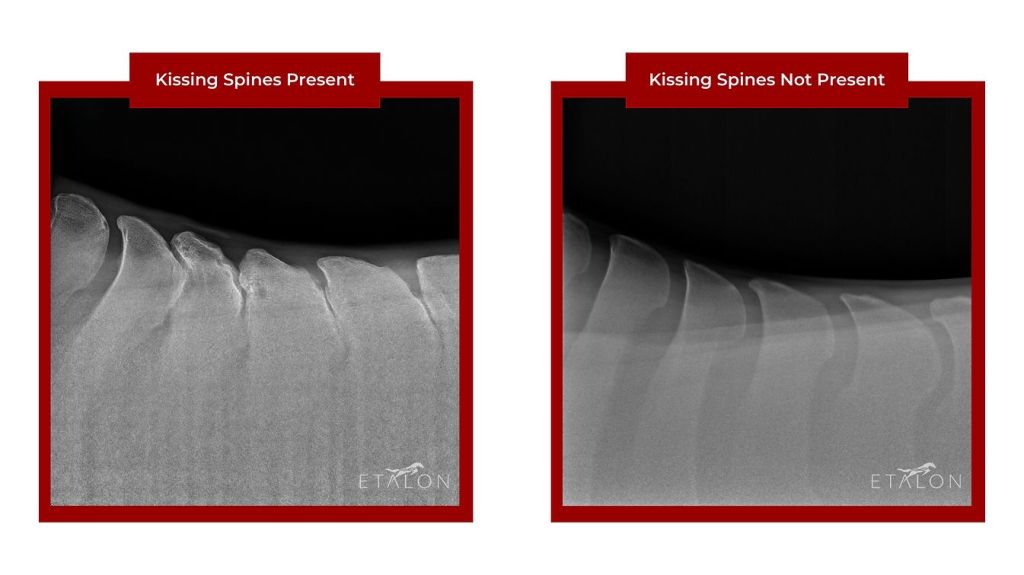

Il termine medico è Overriding Dorsal Spinal Processes (ORDSP) ma più comunemente si parla di kissing spines, letteralmente “vertebre che si baciano”: si tratta di una condizione in cui infatti i processi spinosi di queste, ad opera di diversi fattori, si avvicinano arrivando a toccarsi o, nei casi più gravi, a sovrapporsi.

Per diagnosticare le kissing spines solitamente si ricorre alla radiografia, ma anche esami termografici e la scintigrafia ossea sono pratiche utili per avere un quadro più completo della situazione.